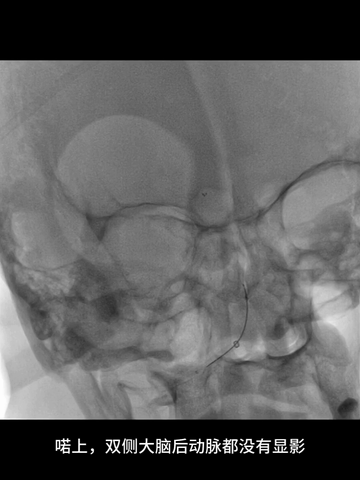

取栓后造影示:基底动脉再通,如之前预判,其管径确实细小;同时造影剂逆流至左椎动脉V4段,显示其管径明显纤细。

中间管回撤至右V1开口处造影示:V1曲折处未见损伤征象。

8、考虑到双胚胎后交通时,基底动脉管径一般比较小,故回收取栓支架时6F中间管只是行至基底动脉近端,未敢深入其中。

考虑到双胚胎后交通,基底动脉管径一般比较小,故回收取栓支架时6F中间管只是行至基底动脉近端,未敢深入其中。